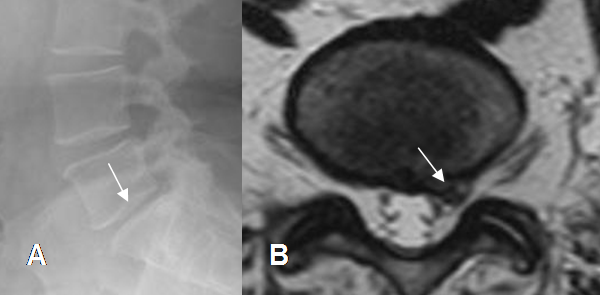

El efecto de masa y la compresión de las raíces nerviosas, no son los únicos responsables de la radiculopatía. La inflamación, factores inmunológicos y cambios vasculares, son factores que contribuyen al dolor. (20). (Fig 82 y 83).

Fig 82. Efecto de hernia.

RM axial en T2. Prominencia asimétrica sin contacto con las raíces y que ¨teóricamente¨, no debe ocasionar síntomas.

Fig 83. Efecto de hernia.

RM axial en T2. Prominencia asimétrica (Flecha gruesa), que desplaza y comprime las raíces posteriormente. (Flecha delgada).